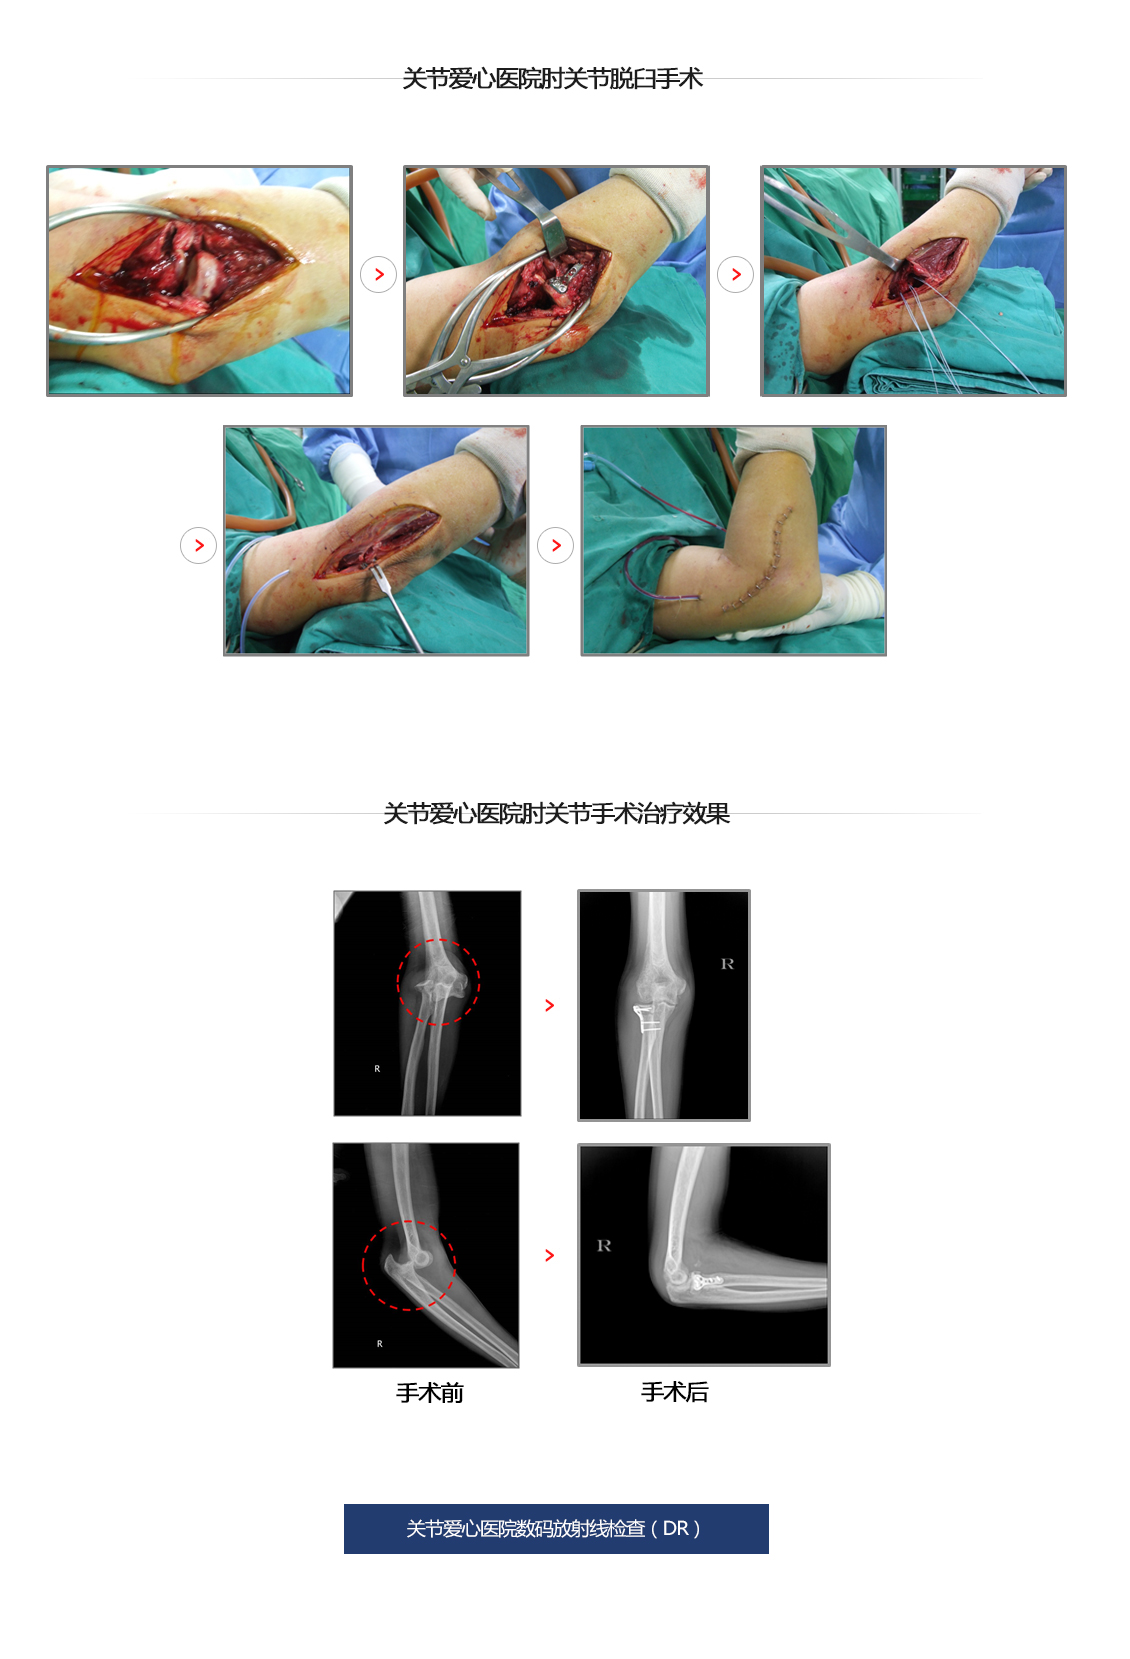

胳膊肘关节骨折